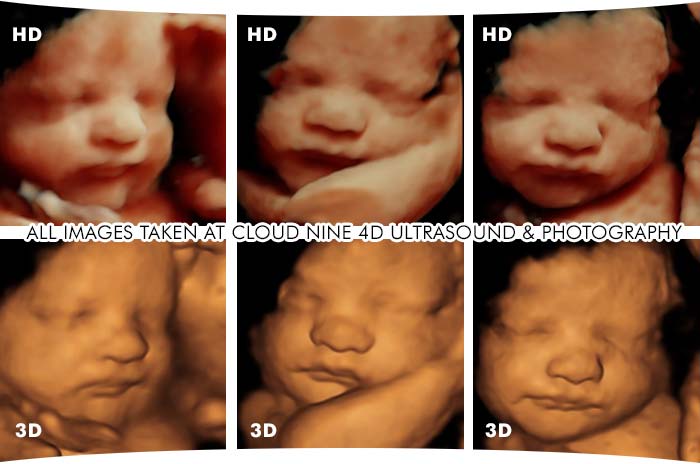

3D Ultrasound / 4D Ultrasound - Kalamazoo and Grand Rapids, MILos Ultrasonidos 4D son una forma emocionante y única de experimentar la alegría del embarazo. A diferencia de los ultrasonidos convencionales, los Ultrasonidos 4D utilizan una tecnología de imagen más avanzada que permite ver al bebé en tiempo real, como si estuvieran viendo una pequeña película. Este tipo de ultrasonido utiliza imágenes tridimensionales y en movimiento que muestran la textura, la forma y los movimientos del bebé en el vientre.

Los Ultrasonidos 4D ofrecen una visión tridimensional en tiempo real del bebé en el vientre, lo que permite ver su aspecto, movimientos y faciales. Esto es mucho más detallado y realista que las imágenes en 2D que se han utilizado tradicionalmente, y permite una interacción más cercana con el bebé antes de su nacimiento.